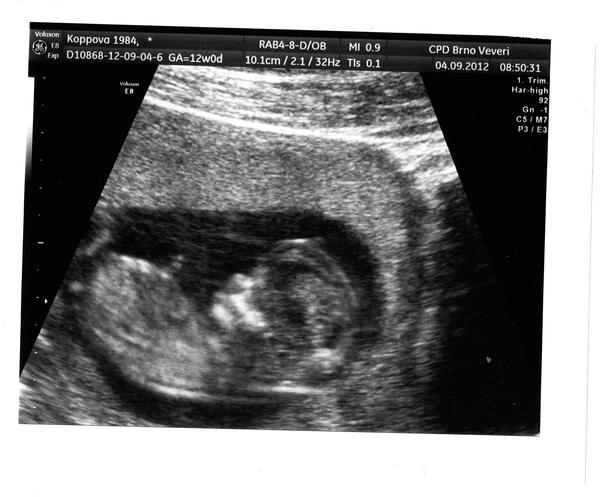

IVF: 1.IVF Unica srpen 2010 ( zamlklé těhu), 1.KET - neg., 2.IVF Unica září 2011 - neg. , Reprofit - minimálka květen 2012 - nedošlo k ET ( embrya zamražena), 2.KET Reprofit - čeká se, 30.6. KET-Moc držím pěstičky-A NALEZENY //, TP: 18.3.2013.:-) a ještě jednou mooooc gratuluju mamino -Dneska screening DRŽÍM VŠECHNO CO MÁM!!!!!!

@drndapetka jé tak to gratuluji,vy jste skoro o 3 cm větší než my,doktorka mi říkala,že jsme zatím malincí,že budeme drobnější asi, posunuli ti termín někam?

@fretecka nééé, my máme od hlavičky k zadečku 5,7cm, těch 9-10cm je bráno s nožičkama,měla jsem původně termín 19.3.2013 a posunuli mi ho o jeden den dřív na 18.3.2013. Dnes mi strašně ale strašně bolí bříško, nevím jestli to nemůže být z toho ultrazvuku, jak doktor tlačil. Když ležím, tak je to dobrý, ale když vstanu, tak začnou ty křeče, úplně stejně jak při menstruaci, možná i horší...myslíš, že je to o.k.?

@drndapetka no to my máme 8,1 nám ho posunuli o 5 dní dál. jojo s tím bříškem ted taky trpim,asi se roztahuje děloha,mě už bolí týden takto